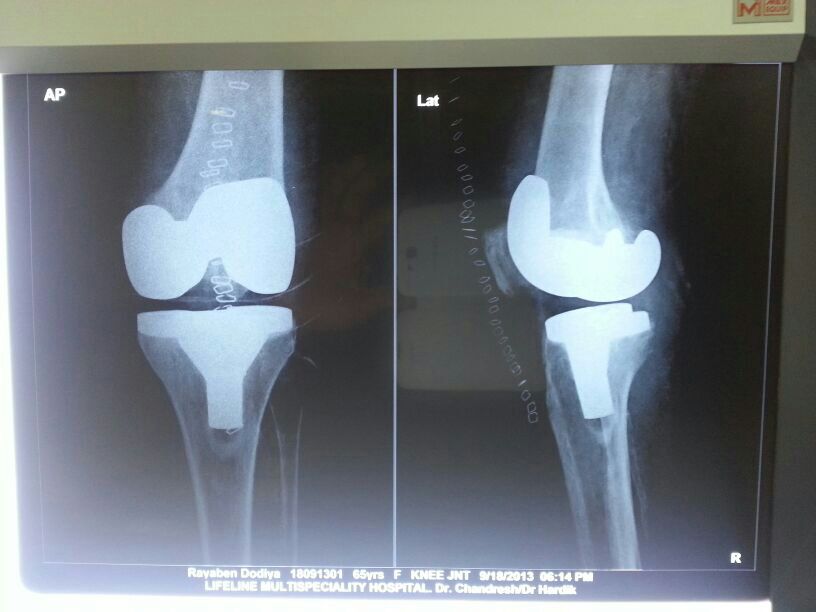

Knee Replacement

"Sunderbhai, SC IC Fumer fracture surgery performed by Dr. Chandresh Sharma at Lifeline